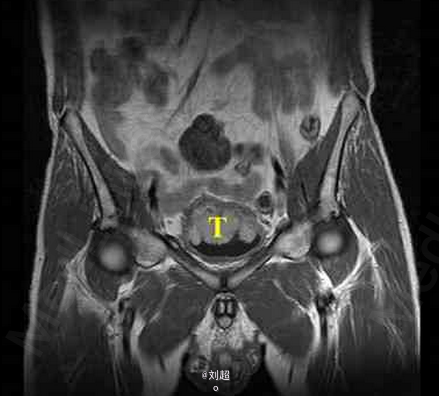

患者尿频、尿急、尿痛,有肉眼可见血尿 辅查MRI,平扫见膀胱侧壁和前上壁呈菜花样突入腔内,T1WI呈低信号,T2WI呈稍高信号,增强后肿块明显强化

膀胱移行细胞癌 处理:手术配合放疗、化疗